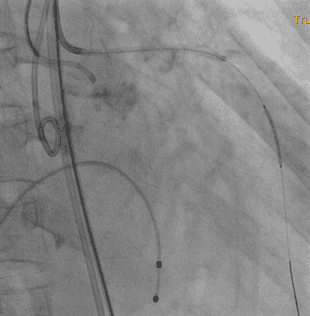

近日,南华大学附属第二医院成功为一名72岁的女性患者进行了经导管主动脉瓣置换术(TAVR)。患者体重38kg,因胸闷、气促2月余,加重7天到经诊断为心脏瓣膜病、主动脉瓣重度狭窄、心功能IV级。 前期经积极的药物治疗,但患者主动脉瓣重度狭窄并少中量返流,二、三尖瓣少中量返流,肺动脉高压,左心功能严重减低(26%)且左冠开口位置偏低,定位一旦不精准,整个左冠闭塞,后果是灾难级的。因患者衰竭状态实在不能承受外科SAVR。医院第一时间组织院内外专家进行MDT(多学科会诊)充分讨论,决定开展经导管主动脉瓣置换术(TAVR)进行治疗,并制定详细的手术方案。

术中,采用了两个新技术保护左冠;“烟囱”技术和对合缘对齐技术,同时邀请ECMO全程为手术护航,一旦出现循环崩溃等紧急情况时迅速提供体外膜肺氧合支持,保障患者生命体征。在麻醉科、心外科、普通外科血管外科专业、超声心动图室等的支持下经过团队的合作,术后主动脉跨瓣压差显著降低,无明显瓣周漏,左室射血分数即刻得到改善,术前低血压状态逐渐改善,恢复到同龄人状态。